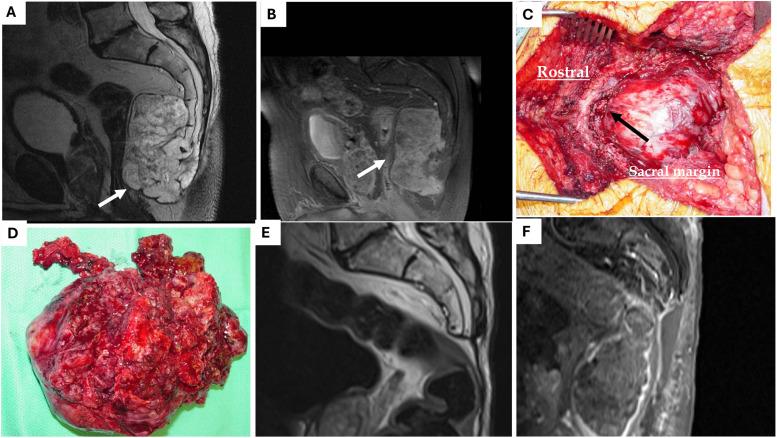

颅底及脊髓脊索瘤的外科治疗:病例系列及文献综述

Surgical management of skull base and spinal chordomas: A case series with comprehensive review of the literature.

Chordomas are rare, slow growing, locally aggressive malignant bone tumors that arise from remnants of the embryonic notochord with variable presenting symptoms depending on tumor location.

脊索瘤是一种罕见的、生长缓慢的、具有局部侵袭性的恶性骨肿瘤,起源于胚胎脊索的残余组织,其症状因肿瘤位置而异。